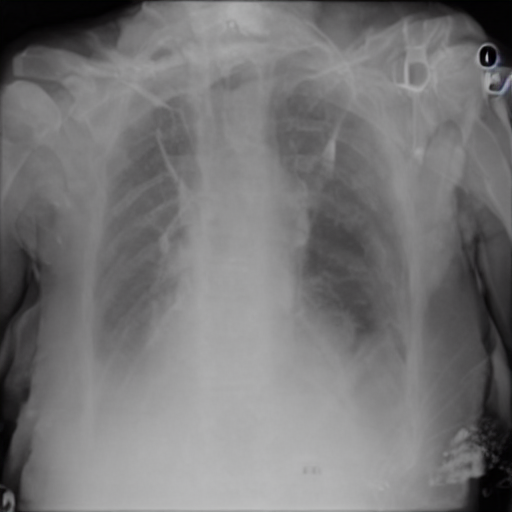

4.3.1 Zero-shot Induction of Non-Healthy Counterparts

Despite our model being trained for healthy counterpart generation, we may consider instead a reverse of this process, i.e. the induction of a specific disease within healthy scans using the same experimental pipeline. In particular, we can consider the capacity to induce disease via the latent language capacity of the model.

As an instance of this, the trained model was prompted in the generative setting for “carcinoma" in relation to a healthy image. The result is shown in Figure 4 alongside the real healthy scan and a separate real-case carcinoma. It is clear that the induced disease is visually comparable to that of the real case despite it’s absence from the training set. We propose that this capability arises as a result of a the internal correlation of the domain-adapted text encoder to that of the visual domain via the visual model, given that the domain-adapted text encoder is trained on the full panoply of Radiology reports.

To evaluate this in more detail we examine a less localised condition: Cardiomegaly.

Zero-shot evaluation: Cardiomegaly

The disease cardiomegaly (enlargement of the heart) was not present in the training data; to evaluate zero shot induction in this context, we take real images from the small version of the Chexpert[52] dataset (from https://www.kaggle.com/datasets/ashery/chexpert). Thus, 8060 images of positively identified cases of cardiomegaly were used as the reference image set for real cardiomegaly. Correspondingly, for each of the healthy images from the COVID 19 database, an induced version was generated by the model with the prompt “Cardiomegaly". FID scores between the real cases of cardiomegaly from the Chexpert dataset and the generated images are given in Table 4.

The FID scores in Table 4 indicate that the generated cardiomegaly images do not have a large distance (using the 275.0 baseline of the Roentgen[30] study) from the real images from which they were generated, suggesting appropriate perturbations were made and the generations were reasonably close to the real cardiomegaly set from the Chexpert dataset.

Interestingly, while generation across different settings of the visual diffusion hyperparameters Strength & Guidance-scale did not have a very significant difference on FID scores evaluated across the full range of image sets, visual differences for individual images could be more significant, as highlighted in Figure 5 for two different settings of the respective hyperparameters. This is presumably due to the different aspects specific to individual patient image (such as the prior health of the patient, structural variances due to age, recording equipment, size etc) acting to mimic hyperparametric variation, which primarily appears to affect the opacity of the induced material for hyperparameter settings ranges consistent with good image generation (in general, the Strength hyperparameter give scope for larger perturbation from the original image during diffusion, while Guidance-scale determines the intensity of text prompt conditioning; optimal settings of these parameters are inherently disease-specific given the wide variation in the amount of pixel opacity needing to be added in the disease induction setting of the pipeline).

(For an additional comparison baseline, we include results for induction of disease that are within the training set, namely viral pneumonia and COVID19. Results are given in figure 6).